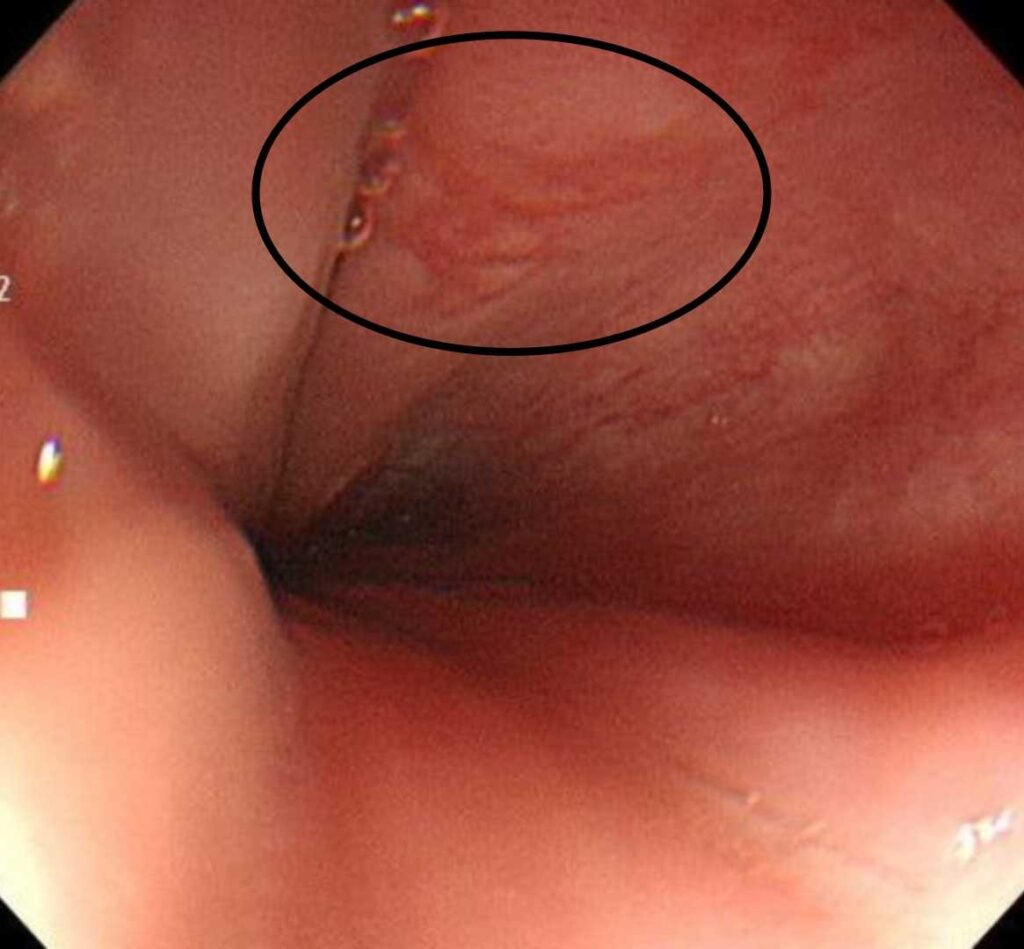

- 早期食道がん

「たまたま受けた」胃カメラで早期発見 → 内視鏡治療で根治。症状の乏しい段階でも拾えるのが定期検査の強み。